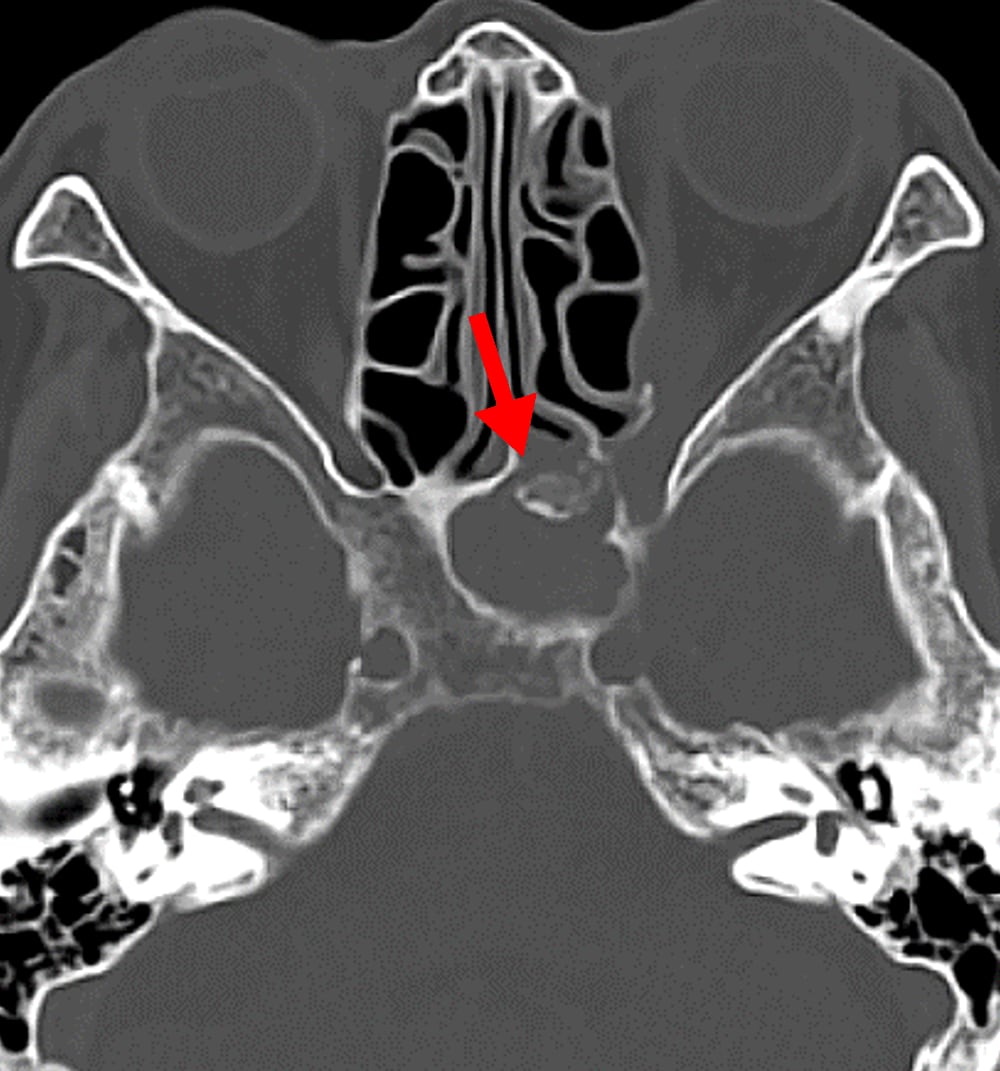

1か月前からの左眼痛、2週間前からの視野異常があり、前医で蝶形骨洞真菌症と診断された。視力障害の急速な進行と左内側視野欠損を来たしたため、当院に紹介された。造影CTにて左蝶形骨洞から左海綿静脈洞・眼窩尖部に浸潤する浸潤性真菌症を指摘された。緊急手術が施行され、病変から糸状様真菌が検出された。

急性浸潤性真菌性副鼻腔炎は臨床経過が4週間以内と急速に進行する病態を示す。骨破壊を伴って副鼻腔から眼窩・海綿静脈洞・頭蓋内に浸潤が見られる。また血管侵襲性が強く、時に仮性動脈瘤形成や動脈狭窄・閉塞、血栓形成を引き起こす。血管に沿って進展し、骨破壊を伴わずに副鼻腔外に炎症が浸潤する場合がある。

造影CTでは骨破壊の有無、副鼻腔外への炎症浸潤、また仮性動脈瘤や動脈狭窄・閉塞、血栓形成を評価する。海綿静脈洞は動脈性病変、静脈洞血栓、炎症浸潤が混在する可能性があり、早期動脈相・後期動脈相・平衡相を撮像することでこれらを鑑別する。